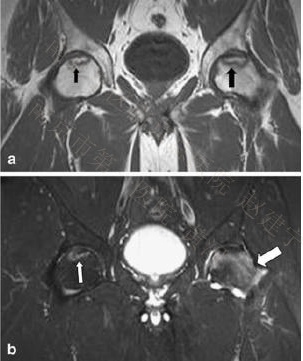

58岁男性。(a, b) T1-W及T1快速翻转恢复图像(STIR)均可见右侧股骨头内弥漫性的骨髓水肿(粗箭头),同时软骨下可见线性的低信号(小箭头),甚至髋臼区亦可见骨髓水肿信号(细长箭头)。(c) 脂肪增强抑制T1-W自旋回波图像(SE)显示股骨头及髋臼弥漫性骨髓水肿信号(箭头),软骨下线性改变(黑箭头)以及髂腰肌滑囊炎性改变信号(粗箭头)。(d) 11个月后T1 STIR图像见骨髓水肿区已完全消失。

45岁,长期服用皮质类固醇激素,左髋疼痛2月。T1-W(a)及脂肪抑制T2-W像(b)均可见左髋股骨头内有典型的条带状信号(粗黑箭头)以及弥漫性的骨髓水肿(粗白箭头);在无症状的右髋中也可见到这一典型的条带状信号(均为细箭头),但并无骨髓水肿改变,表明ONFH尚处于病变的早期阶段。